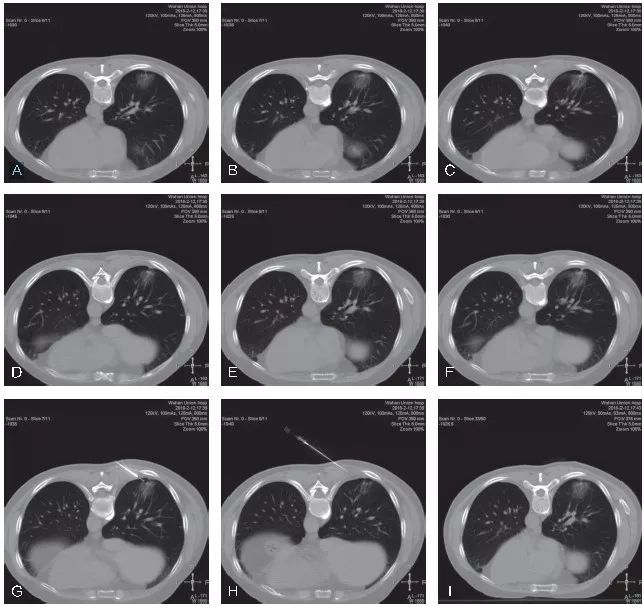

不良事件的发生率在可接受范围内。气胸是经胸廓细针穿刺活检最常见的并发症,发生率为16.0%~51.8%。在341位患者中,只有7位患者需要留置胸腔引流管。咯血发生率为8%~23%,没有患者需要治疗。从穿刺技术层面上来看,GGO的穿刺活检与普通肺结节的穿刺活检基本类似,同样需要注意避免引起气胸或出血的危险因素,从总体诊断效能及并发症发生情况来看,与普通肺结节大体一致。但也有部分研究者认为,GGO本身为经皮肺穿刺活检发生出血的一个危险因素,分析其可能的原因主要是GGO的体积通常较小,在使用全自动活检枪进行切割式活检时会损伤到更多的肺组织及肺内血管,造成较为明显的肺内出血。我院完成的GGO穿刺活检同样表现为较为明显和广泛的肺内出血征象(图5-2~图5-4)。这一点在小结节的穿刺活检中同样经常出现。因此,我们要求对于小结节/GGO的穿刺活检,务求“一击必中”。因活检取材易出现较明显的肺内出血征象,如取材不满意,即使再次进行CT扫描,亦可能无法为我们提供有效的影像引导,导致最终无法进行有效的调整,导致活检取材失败。

图5-2 A~C. 显示患者右肺下叶后基底段mGGO,选取俯卧位进行穿刺活检;D~F. 显示穿刺活检的实时CT影像,选取最短的穿刺路径,并尽量使同轴穿刺针与较粗大的肺内血管平行。图中显示同轴穿刺针到达预设位置,并未紧邻靶结节表面,为活检预留好空间,以免损伤该结节远端的肺内血管;G~I. 显示完成活检后,拔除同轴穿刺针。再次进行CT扫描,见靶结节活检区域明显的肺内渗出性改变,提示较严重的肺内出血。病理结果示:(右肺)浸润性腺癌